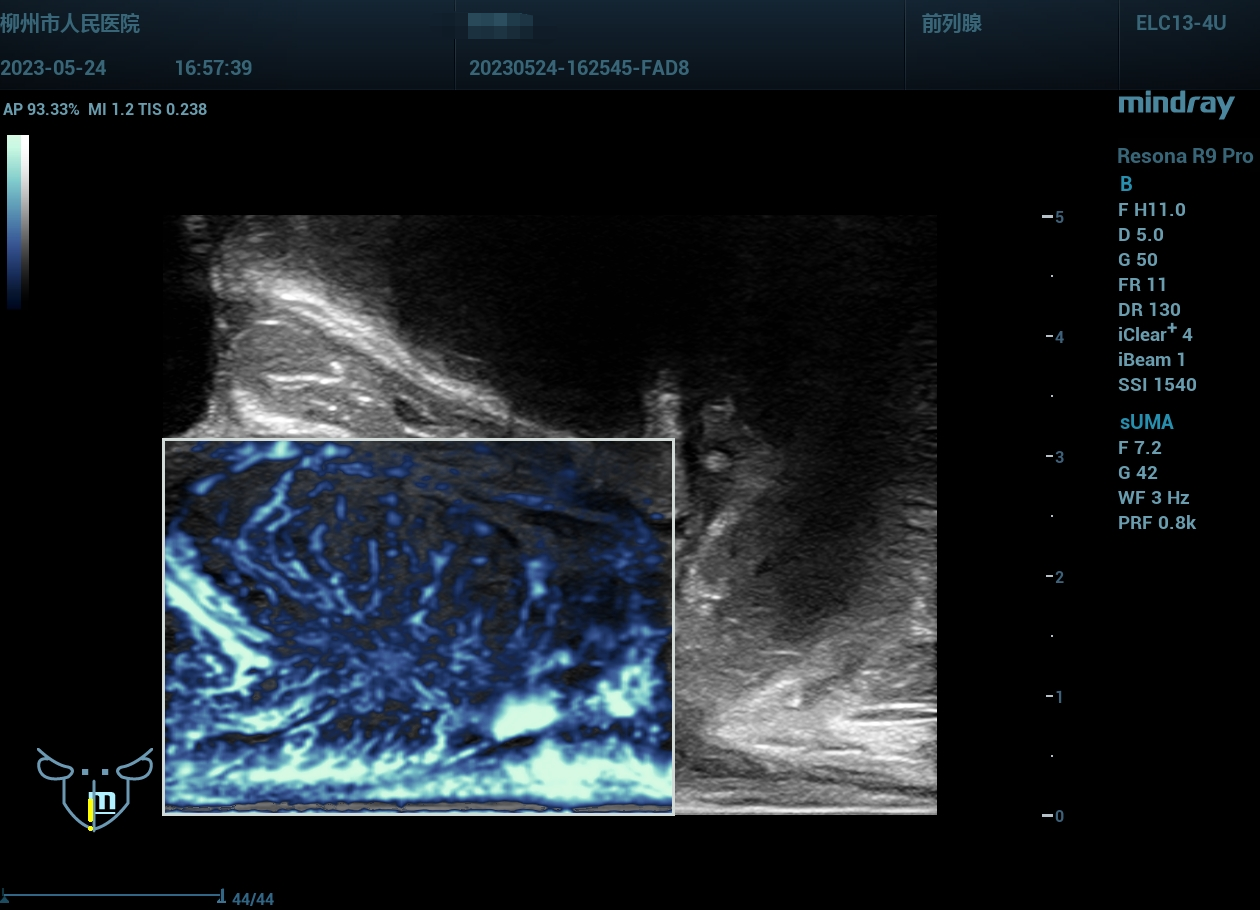

经会阴前列腺穿刺,与MR融合导航。